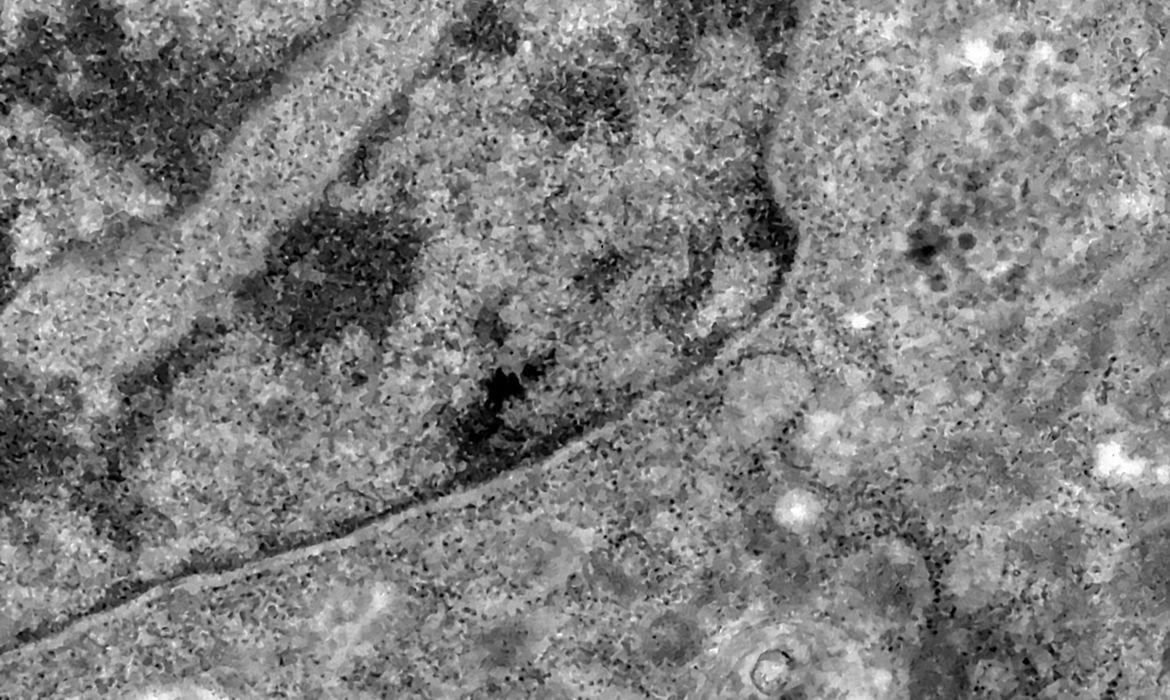

Nos casos analisados, constatou-se que a variante é portadora de dezenas de mutações genéticas que podem afetar os índices de contágio e de letalidade. A OMS, entretanto, afirmou que ainda não há estudos suficientes para afirmar as propriedades da Ômicron, mas que já existem esforços científicos acelerados para estudar as amostras. Um time de cientistas de universidades da África do Sul está decodificando o genoma da Ômicron, juntamente com dezenas de outras variantes do novo coronavírus.

Tulio de Oliveira, diretor do Centro para Respostas e Inovações Epidêmicas da universidade de KwaZulu-Natal, afirmou em coletiva de imprensa que a variante Ômicron possui “uma constelação incomum de mutações”. A variante Delta, por exemplo, possuía duas mutações em relação à cepa original do novo coronavírus, enquanto a Ômicron possui cerca de 50 – 30 delas localizadas na proteína Spike, responsável por infectar células saudáveis, explicou o brasileiro.